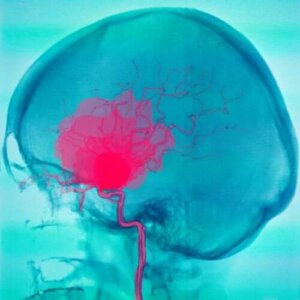

Hemoragiile subarahnoidiene și subdurale

În hemoragiile subarahnoidiene și subdurale, sângele curge din vasele de sânge aflate în spațiul dintre straturile meningelui. Prin urmare, hemoragia afectează țesutul cerebral.

Hemoragiile subarahnoidiene

Hemoragiile subarahnoidiene presupun acumularea de sânge între arahnoidă și pia mater. Sângele provine, de obicei, din artere. Există numeroase cauze care duc la apariția acestui tip de hemoragie. Cea mai frecventă este ruperea unui anevrism.

Anevrismele se manifestă adesea înainte de rupere prin dureri de cap sau chiar crize epileptice. Într-o treime din cazuri, factorul declanșator este fizic, dar are și o componentă emoțională. În plus, un anevrism se poate rupe dacă bolnavul stă în soare prea mult timp.

După ruperea unui anevrism, se declanșează hemoragia subarahnoidiană. De obicei, această problemă apare între 40 și 60 de ani și prezintă următoarele simptome: